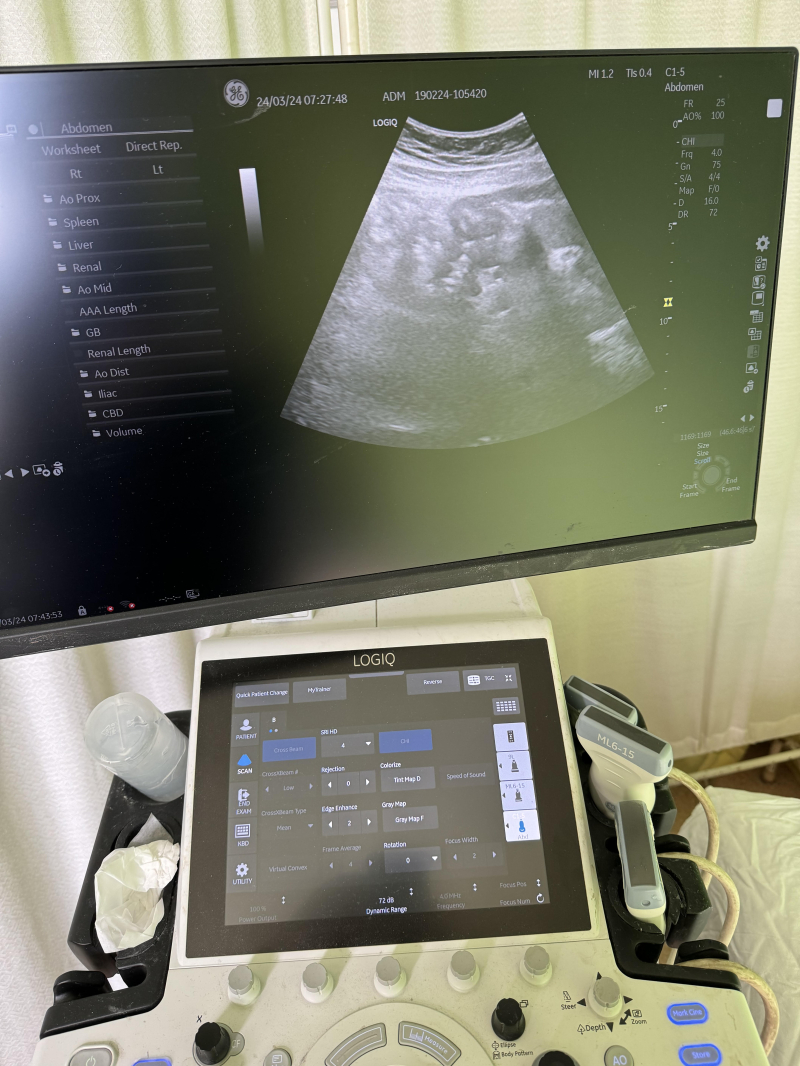

U vranjskom Zdravstvenom centru u nedelju je obavljeno 45 pregleda dojki i 178 prostate.

Trideset žena je upućeno na dodatni pregled mamografom.

Što se PSA testova tiče, u Vranju ih je urađeno 60, u Bujanovcu 31, Trgovištu 26, Vladičinom Hanu 51 i Preševu 10 .